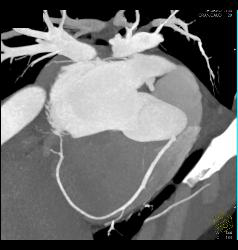

What is a mediastinal mass?

Mediastinal masses are caused by a variety of cysts and tumors; likely causes differ by patient age and by location of the mass (anterior, middle, or posterior mediastinum). The masses may be asymptomatic (common in adults) or cause obstructive respiratory symptoms (more likely in children).

How do you differentiate mediastinal mass?

CT and MRI are important for the diagnosis of mediastinal masses. The location and tissue characteristics on imaging studies are critical to narrow down the differential diagnosis of mediastinal masses. Symptomatology and patient age affect the likelihood of malignancy.

What causes mediastinal mass?

Q: What causes mediastinal tumors to form? A: Depending on etiology, a mediastinal tumor can be caused by an enlarged lymph node, or a gland such as the thymus, thyroid, or parathyroid. It can also be caused by a cyst originating from the pericardium (the sac that houses the heart), the bronchus, or the esophagus.